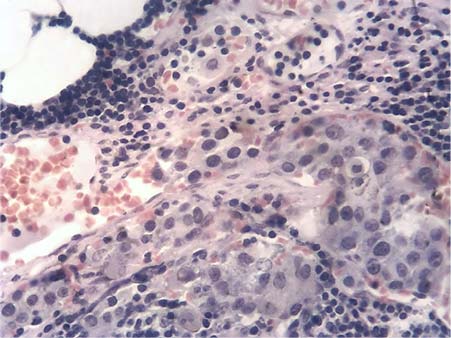

В результате изготовления серийных срезов с реакцией МКАТ против пан-цитокератинов был выявлен 551 непоражённый ЛУ, 38 — с наличием изолированных клеток опухоли или их кластеров (рис. 1), 122 — с микрометастазами (рис. 2), 479 — с метастазами различного объёма и 73 ЛУ, полностью замещённых опухолевой тканью. В двух последних случаях метастазы хорошо определялись и без иммуногистохимического исследования. Сеть кровеносного микроциркуляторного русла ЛУ выявлялась по экспрессии МКАТ против CD31 в эндотелии и против коллагена IV типа в базальных мембранах сосудов (рис. 3).

Рис. 1. Изолированные клетки опухоли и их кластеры. Реакция с моноклональными антителами против пан-цитокератинов. LSAB-метод с докраской гематоксилином. ×400